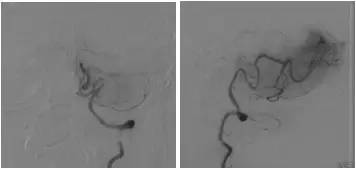

全麻下右股动脉穿刺置入6F动脉鞘,将6F导引导管至右椎动脉V1段,造影:右椎动脉V2段近段及远段狭窄。右椎动脉V4闭塞,右椎动脉V4远段经由脊髓前动脉代偿显影,左椎动脉由对侧椎动脉肌支及脊髓前代偿部分显影(图8)。

图8